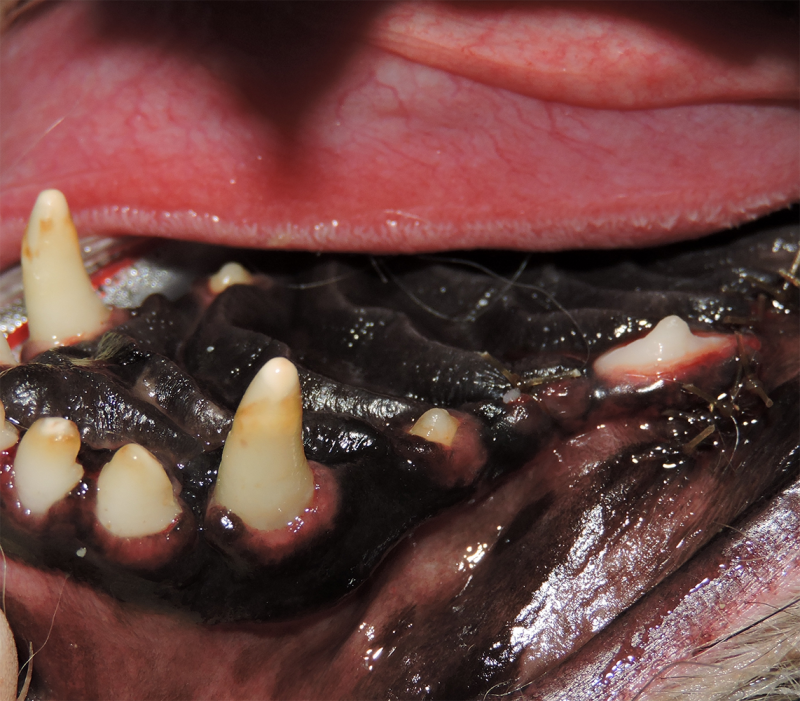

Tooth Resorption

Tooth resorption is a disease process where the body begins to break down the adult tooth. It is widely known to occur in cats but can also occur in dogs. In cats these lesions are thought to be inflammatory, while in dogs they can be more of a replacement resorption process. These lesions can be very painful and should be treated, generally with extraction depending on the type of resorption that is occurring. The disease can be progressive and affect many teeth over several years. It is important to have regular checkups and yearly dental cleanings to monitor for these lesions.